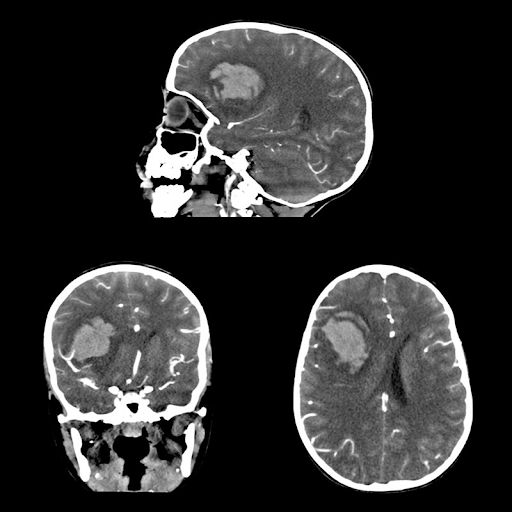

Технология SURE Subtraction

Уточненный алгоритм визуализации и программное обеспечение SURESubtraction повышают качество изображения.